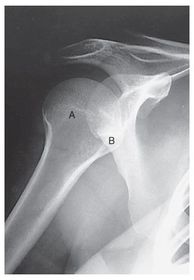

Glenoid Cavity Posterior Oblique Shoulder *nontrauma "Grashey Method" *SPECIAL 40 SID 70-85 kVp 10x12 IR grid CR perpendicular to IR, centered to scaphohumeral joint - 2 in inferior and medial from the superolateral border of shoulder *expose on suspended breath *pt obliqued 35-45 degrees toward the affected side - opens up glenoid cavity

A. coracoid process B. glenoid cavity OR scapulohumeral joint C. spine of the scapula D. acromion